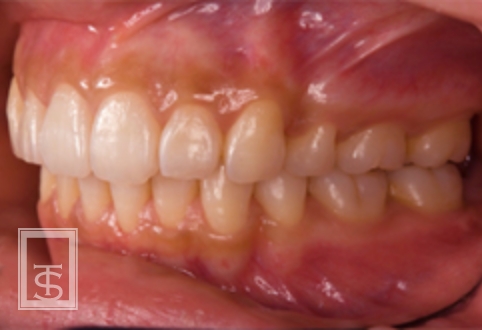

歯軸の重要性

歯軸とは、歯の長軸と上下顎基準平面との角度を意味しています。

審美的改善、機能的安定を獲得するには個人個人に合わせた歯軸の設定が必要です。

また、歯軸の設定は矯正治療時の抜歯判定の基準として用いられます。